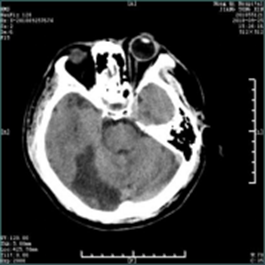

急性脑梗死的教学案例 专业知识 脑梗死(cerebral infarction,CI)又称缺血性脑卒中,是指各种原因所致脑部血液供应障碍,导致脑组织缺血、缺氧性坏死,而出现相应神经功能缺损的一类临床综合征。 案例 孙某,男,主因“发现言语不清、左侧肢体活动不灵1小时10分”入院。患者于14:30左右起床时发现言语含糊不清,吐字费力,口角歪斜,左侧肢体活动不灵,表现为左上肢无法抬起,左下肢无法行走,伴头晕,视物不适,无头痛,无恶心、呕吐,无视物旋转,无一过性黑矇,无意识障碍,无胸闷、气短。为求进一步诊治急来我院就诊。患者今日中午13:30睡午觉时无言语不清,无左侧肢体活动不灵。既往高血压病史10年余,平素血压最高达 210/120mmHg,未规律系统用药;否认心脏病、糖尿病病史。 查体:体温:36.5℃,血压:163/100mmHg,呼吸:20次/分,双肺呼吸音清,心率89次/分,腹软,双下肢无浮肿。神经系统查体:意识清,构音障碍,左侧瞳孔大约5.0mm,右侧瞳孔大约3.0mm,对光反射灵敏,水平眼震,左侧同向性偏盲,右侧头面部麻木,右侧周围性面瘫,伸舌居中,左上肢近端肌力2级,远端肌力2级;左下肢近端肌力3-级,远端肌力3-级,右侧肌力5级,四肢肌张力正常,腱反射(++),左侧Babinski(+),颈软,克氏征(-),NIHSS评分:9分。急查头部CT示:右侧枕叶低密度影。